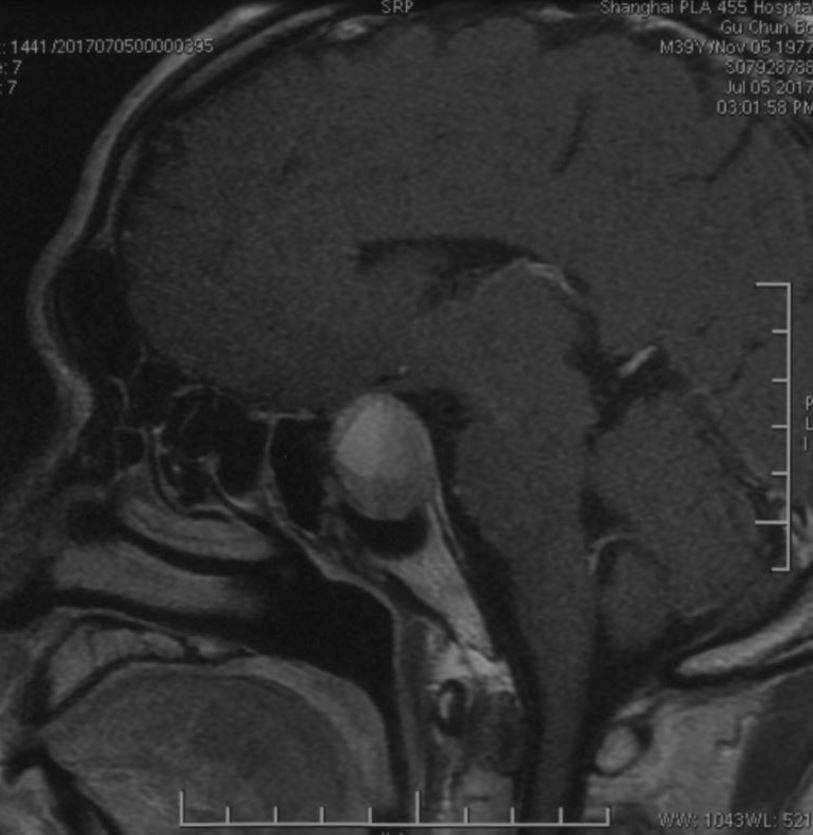

鞍区磁共振检查发现:鞍区肿瘤卒中可能,肿瘤侵犯双侧海绵窦、颈内动脉,鞍隔被顶起,鞍底部分塌陷。

矢状位增强